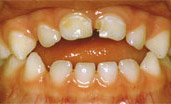

Отдельного следует отметить состояние детей с синдромом Дауна. Хорошо известны лицевые признаки при этой патологии у взрослых пациентов: недоразвитие средней зоны лица, макроглоссия, макрогения, дыхание ротовое, постоянное межзубное положение языка. У всех обследованных детей, имеющих названную патологию соотношение челюстей было выявлено нейтральное, но дыхание - ротовое, а, следовательно, у этих детей наблюдалось постоянное межзубное положение языка, тонус которого резко снижен. Цель использования вестибулярной пластинки с активатором для языка в этом случае – контролировать тонус и положение языка, стремиться к тому, чтобы губы ребенка в покое были сомкнуты, что должно помочь сохранить существующее нейтральное соотношение челюстей и стимулировать носовой тип дыхания. В течение 3-4 месяцев применения пластинки у всех наблюдаемых детей сохранялось нейтральное соотношение челюстей, тонус языка постепенно улучшился, положение его нормализовалось. Для окончательных выводов наблюдение будет продолжаться.